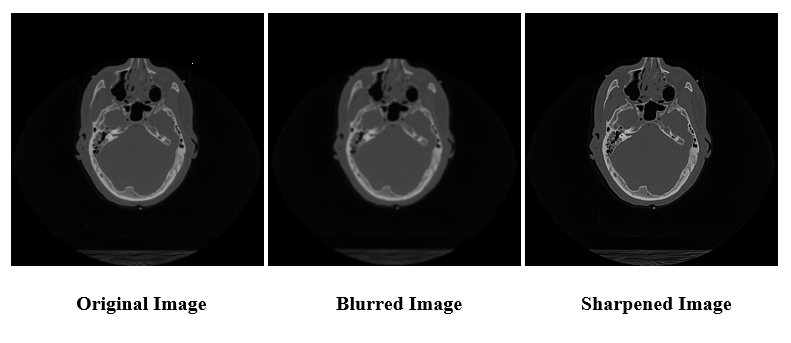

When run with the command line arguments --operation=blur --kernel_size=5 --repetitions=11 head_ct.png, both the original C++ and new DPC++ convolution program are expected to return the same resultant image. To sharpen an image instead of blurring it, blur can be replaced with sharpen. Figure 3 shows example outputs of the program run using an image of a brain from a CT scan:

Figure 3. Original image vs. output images